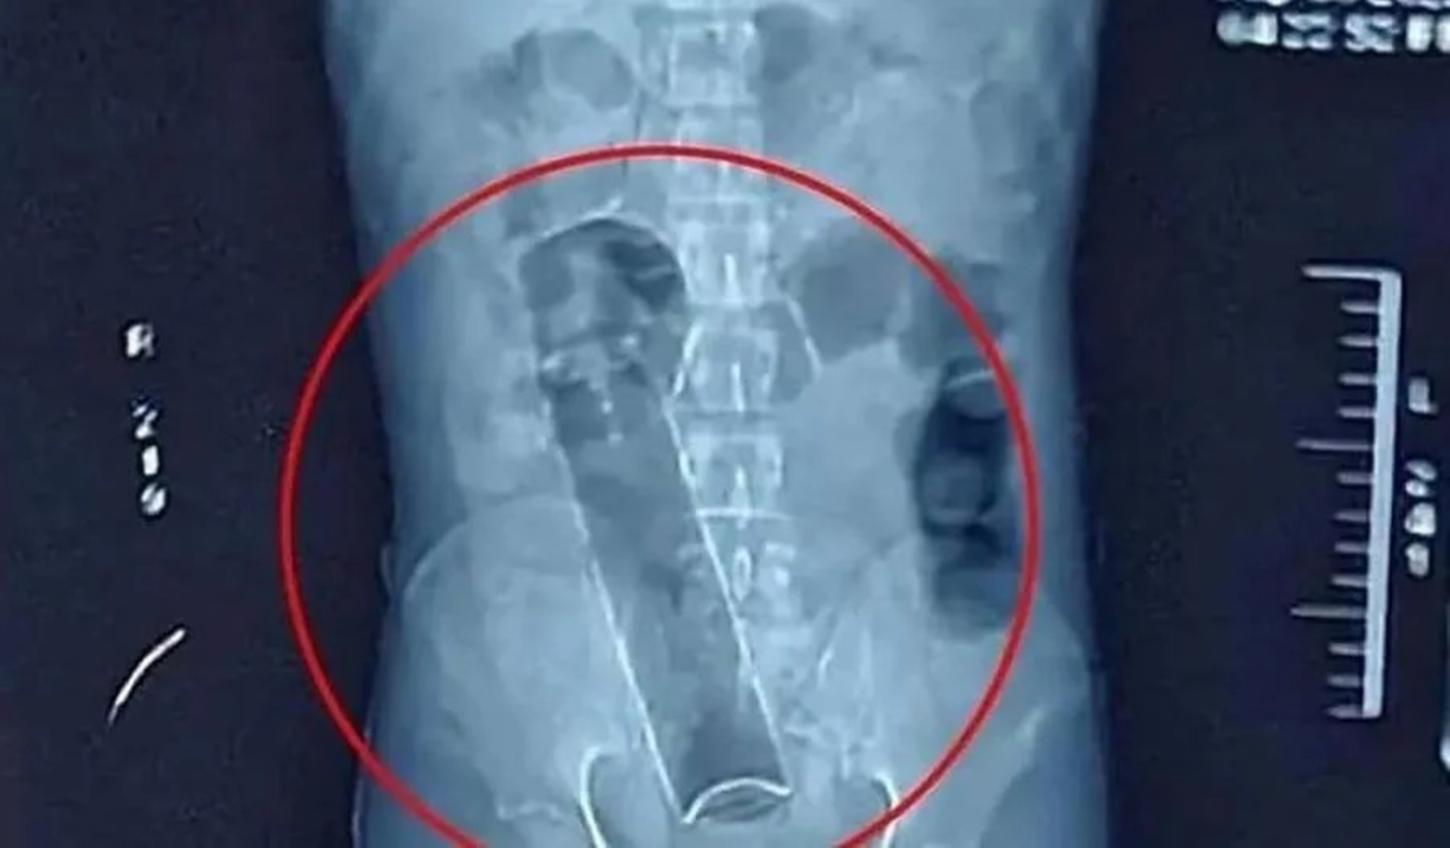

Um homem recorreu ao atendimento médico de urgência na madrugada desta última quinta-feira (13) após um frasco de desodorante ficar preso em seu ânus em Ji-Paraná, segundo município mais populoso de Rondônia.

No local, a equipe médica realizou avaliação clínica e radiológica para identificar a posição do objeto, conforme protocolo adotado em casos de corpo estranho retal. O desodorante, então, foi removido com procedimento médico específico, sem precisão de intervenção cirúrgica.